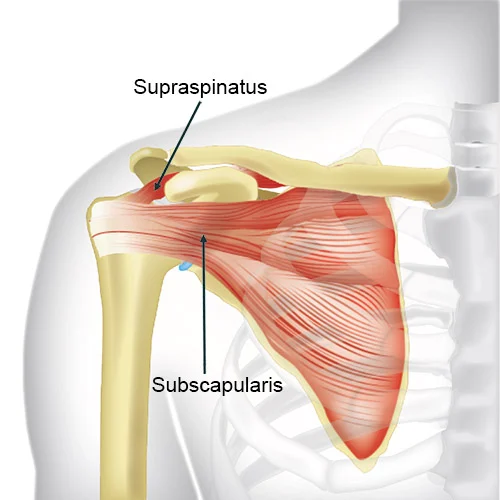

The patellar tendon connects the kneecap to the shin bone and is put under enormous stress during jumping, landing, and kicking. Repetitive overload causes degenerative changes (tendinosis) rather than true inflammation the tendon becomes thickened, disorganised, and painful. PRP injected precisely into the tendon under ultrasound guidance stimulates a healing response that physiotherapy alone cannot achieve.

Similar degenerative changes in the quadriceps tendon (above the patella) present as anterior knee pain, particularly in older athletes and individuals with a high BMI. Eccentric loading programmes combined with PRP or prolotherapy yield excellent results.

A friction syndrome causing lateral knee pain in runners the iliotibial band (a thick band of fascia running down the outer thigh) repeatedly rubs over the lateral femoral condyle. Ultrasound-guided injection at the point of impingement, combined with targeted hip strengthening, resolves the condition in most cases.

The popliteus muscle a small but vital stabiliser at the back of the knee can develop tendinosis, producing postero-lateral knee pain, often confused with a meniscal tear. Ultrasound assessment and targeted PRP injection are highly specific for this underdiagnosed condition.